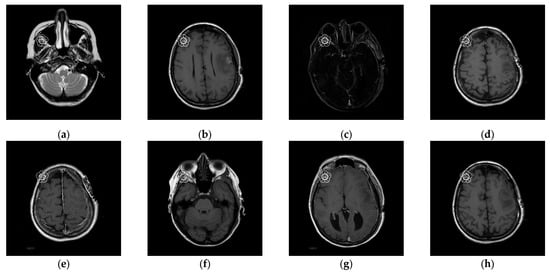

To better align our VUF-MIWS with the practical needs of clinicians for authenticating medical image sources, we conducted a pilot interview at a regional hospital. In this interview, we defined the critical diagnostic reference area of a medical image as the ROI (Region of Interest) and divided it into nine sub-regions, as shown in Figure 14. We then asked seven doctors to indicate their two most preferred locations for visible watermarks. Based on the collected feedback, sub-region A received the highest number of votes (a total of nine), followed by sub-regions E and I (both receiving five votes). Therefore, sub-region A was selected as the watermark position for the first and second experiments. The resulting watermarked images for the first experiments are displayed in Figure 15.

Figure 15. Eight watermarked images. (a) Watermarked 10.png; (b) Watermarked 11.png; (c) Watermarked 14.png; (d) Watermarked 16.png; (e) Watermarked 19.png; (f) Watermarked 26.png; (g) Watermarked 31.png; (h) Watermarked 57.png.